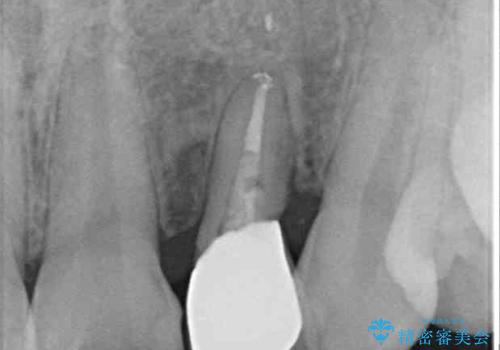

- 他院で前歯の抜歯が必要と言われたとのことで来院された患者様です。

過去にぶつけたことで神経組織が壊死してしまったようで、その後むし歯が進行して歯肉深いところにまで進んでいる状態でした。

まずは部分矯正により歯を牽引し、歯肉や歯槽骨の位置を調整するために歯周外科処置を行い、治癒を待ってオールセラミッククラウンにて補綴治療を行うこととしました。

しっかりとむし歯を牽引したことで、クラウンの周りの腫れが引き、自然な口元に仕上げることができました。